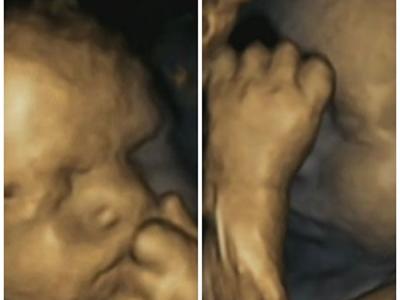

英国研究证胎儿能感应母亲负面情绪

4D扫瞄图片发现母亲发愁时,胎儿摸脸的次数也增加。 (蜘蛛网报道)传统智慧总劝...